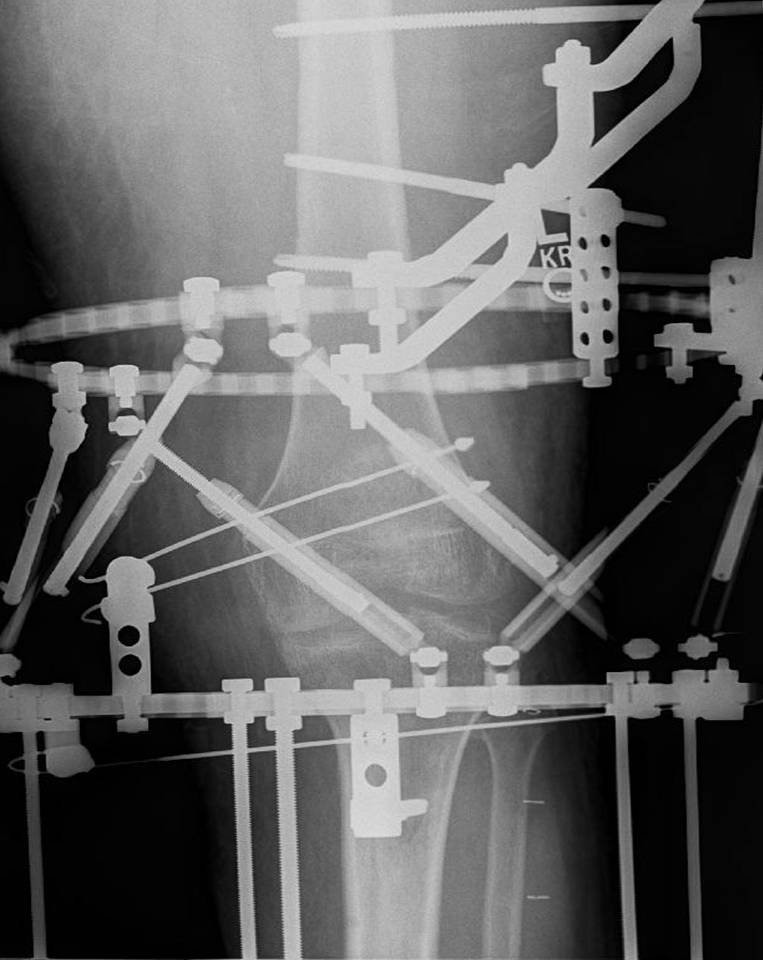

Deformities: Knee

Result After Treatment by Dr. BrinkerThese photographs after treatment show the patient with good knee joint motion and function. He has no pain and was able to walk without assistance.